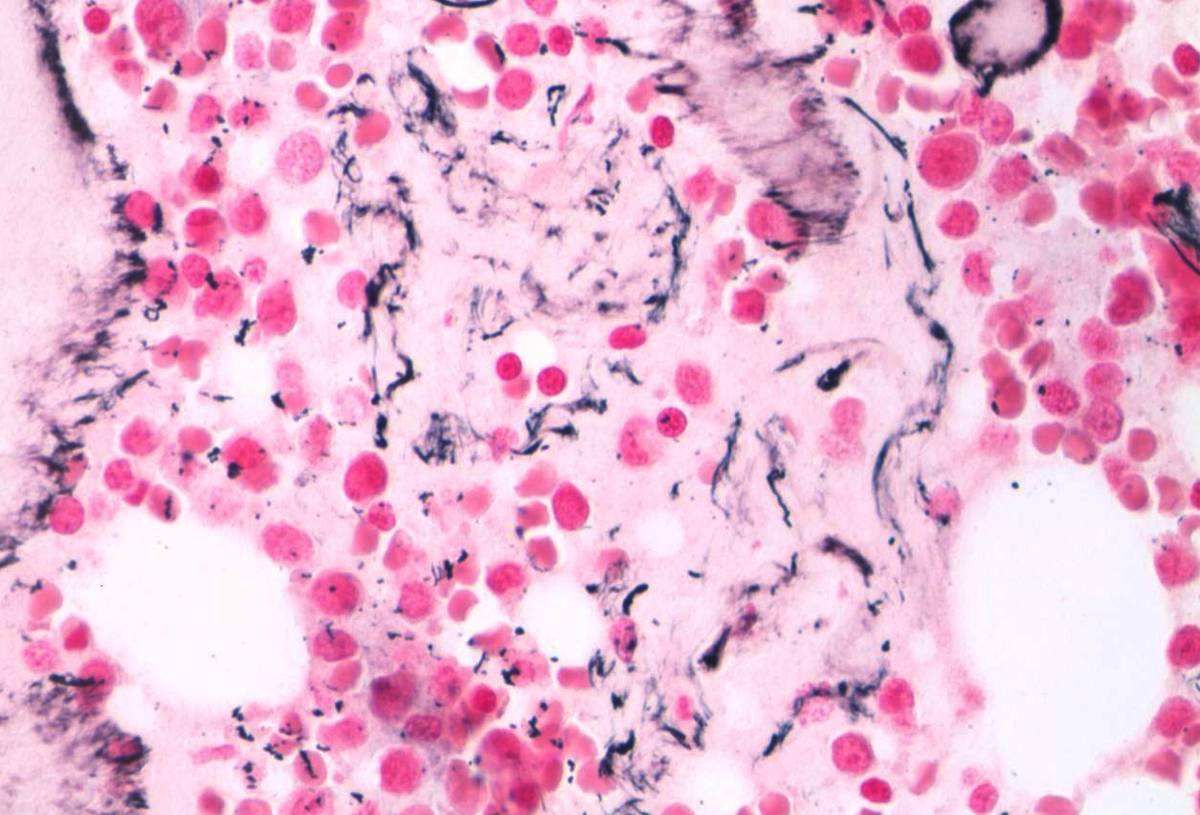

| Biopsy reticulin stain. | ![]() |

Blood smear review demonstrated leukocytosis with numerous blasts, some of which exhibited prominent cytoplasmic blebbing. (Images 1 and 2). Significant drying artifact precluded adequate morphologic characterization of the other peripheral blood elements. Bone marrow biopsy was very limited in size. (Image 3). Most cells appeared to be intermediate and large sized blasts (88% by counts on the biopsy touch imprint). (Image 4). A reticulin stain demonstrates minimally increased reticulin deposition but no overt fibrosis (Image 5). Limited immunohistologic studies performed on the core biopsy demonstrated CD34 positive staining on the blasts (Image 6).